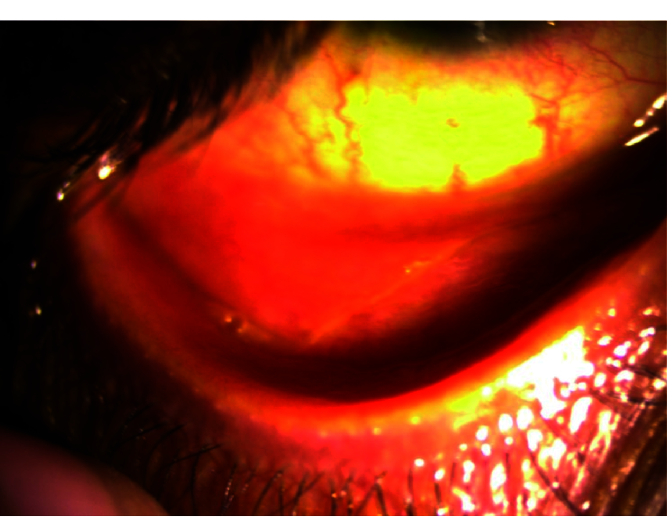

Results: The mean age of the patients was 34.3 ± 11 years. The mean time for the diagnosis of ocular GVHD was 232.8 days (95% CI: 153.6, 311.9). The common findings at the first visit were bilateral blepharitis (n = 5, 17%), meibomitis (n = 4, 13%), and conjunctival congestion (n = 3, 10%). While bilateral cataract was present in one (3%) patient at the first visit, at 18 months, five (17%) patients had bilateral cataract and one (3%) patient had unilateral cataract. Grade 1 (n = 17), grade 2 (n = 9), and grade 3 (n = 4) superficial punctate epithelial erosions (SPEEs) were also observed at the first visit. However, SPEEs were seen in only 11 eyes at 18 months; all of these cases were grade 1 SPEEs. Long-term findings included cataract, telangiectasia, blepharospasm, conjunctival congestion, grade 1 SPEEs, corneal filaments, and tear film debris.

Abstract Image